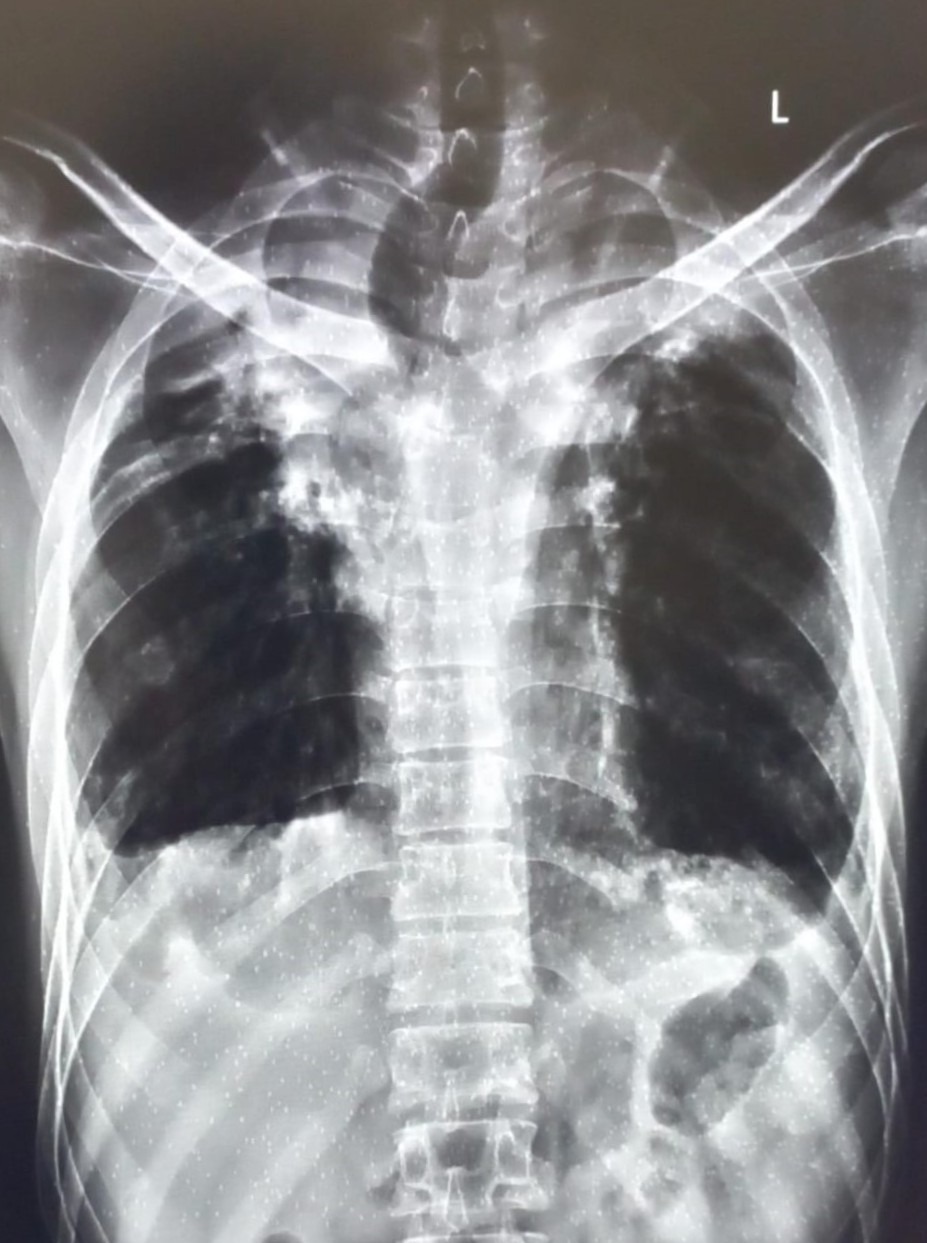

| 4422 | IGGMC, Nagpur, Nagpur | P2 | 29-50 | Vinod Mukardam | Consent taken on Paper | 35 Yrs. |

Provisional Diag : BREATHLESSNESS UNDER EVALUATION

Final Diag : Post TB sequalae (CxR- Bilateral Upper Zone Collapse With Pleural Effusion) |

Post TB Sequelae | Blunting of both lung costophrenic (CP) angles and a trachea shifted towards the right on a chest X-ray | Abnormality visible on x-ray |